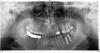

Beeovit Опубликовано 19 августа, 2012 Поделиться Опубликовано 19 августа, 2012 Установили 2 импланта левые нижние 6 и 7 а на них поставили как я понял мост, если я нечего не путаю?Можно ли ставить на два импланта совместно мост или лучше отдельно по коронке?И с доктором оговаривали, что будет по импланту и сумма за каждый а в итоге как я понял мост, может кто пояснит, что делать ведь пломбы на мосту стоят временные пока, а в среду будут ставить постоянные.Может требовать изготовления отдельных зубов или в таком исполнении лучше? Ссылка на комментарий

Bier Опубликовано 20 августа, 2012 Поделиться Опубликовано 20 августа, 2012 это не мост, а соединенные коронки. В боковых отделах так часто делают, это нормально. Ссылка на комментарий